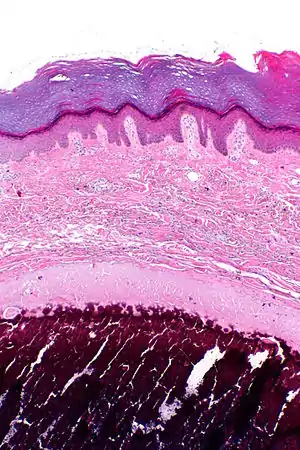

| Micrograph of calcinosis cutis. The calcification is purple (bottom of image). H&E stain. | |